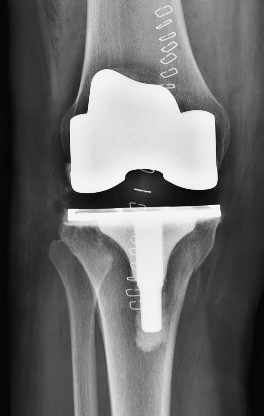

术后次日,患者杨阿姨即在医生指导下进行床旁行走训练,膝关节活动度逐步恢复。杨小海主任医师介绍,全膝关节置换术通过置换磨损的关节表面(类似“换保护套”),可显著改善因关节退变、软骨磨损导致的疼痛,患者术后很快即可恢复日常生活。本次所采用的骨科手术机器人辅助手术,通过三维影像精准规划截骨平面,术中实时调整截骨角度,相较于传统手术,可提升截骨的精准度与假体安放的精确性,缩短手术时间,减小创伤,降低术后并发症风险。杨阿姨术后复查X片显示膝关节假体位置良好,下肢力线合适。